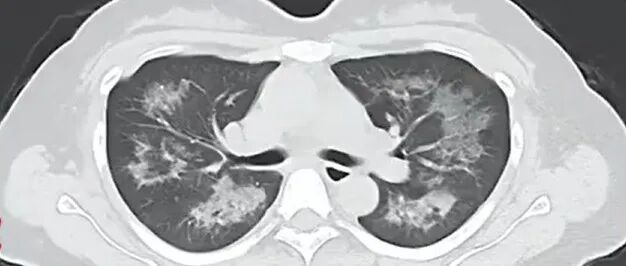

每天用2次定妆喷雾,22岁女主播肺里长满阴影!医生紧急提醒→